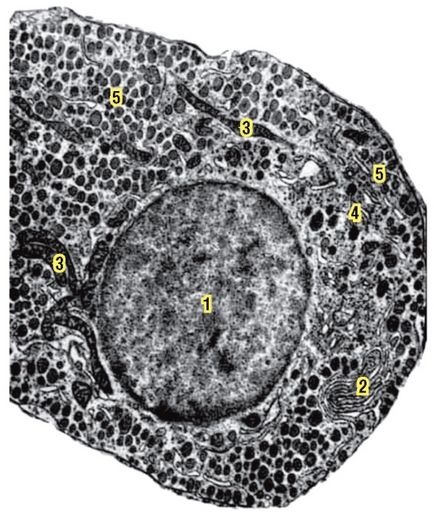

Fig. 167. Microfotografia electronică. Celulă somatotropă acidofilă a lobului anterior al glandei hipofizare (conform lui VS Strishkov):

1 - nucleul; 2 - reticulul endoplasmatic; 3 - mitocondrie; 4 - granule formate; 5 - granule mature